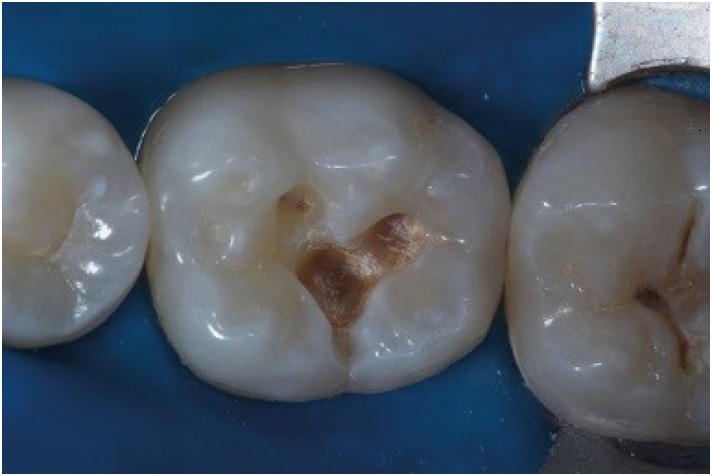

The patient sought the Department of Dentistry of the Federal University of Sergipe (Brazil) for a general oral health assessment. The clinical examination showed a carious lesion on the right mandibular first molar, and the restorative treatment plan was determined based on the clinical and radiographic findings (Figure 1). In order to establish an improved oral and aesthetic rehabilitation, an acrylic resin matrix was produced due to the preservation of the dental anatomy itself (Figure 2). For such production, an insulator was applied with the help of a microbrush on the tooth surface. After manipulating the powder/liquid of the acrylic resin (Jet Classico, Sao Paulo, SP, Brazil) in a paladon recipient (Golgran, Sao Caetano do Sul, SP, Brazil) with a spatula, the resin was applied on the occlusal surface of the tooth. After fixation, the resin was removed and maintained in water to prevent distortion, while the other procedures were performed.

Figure 1

Occlusal view of carious lesion.

rde-45-e9-g001.jpg